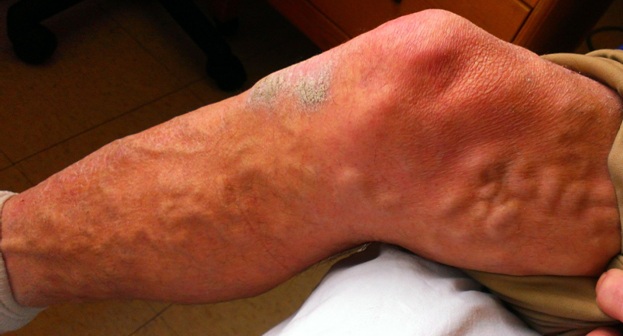

On initial examination in the ER, he was afebrile, blood pressure was 97/67 mm Hg, heart rate 87/min, oxygen saturation of 92% on room air that improved to 97% with 2L/min oxygen supplementation by nasal cannula. Administration of one liter normal saline raised the blood pressure to 118/68 mm Hg. On physical examination, lungs were clear to auscultation, varicosities (clinical class C4a) without tenderness were noted over his legs bilaterally [Table/Fig-1] and small dried lacerations over the tip of his nose and central forehead were observed. The rest of his physical examination was normal. His electrocardiogram (EKG) showed sinus rhythm at a rate of 91 beats/min with incomplete RBBB [Table/Fig-2a,b]. No prior EKG was available for comparison. The incomplete RBBB pointed to right heart strain possibly due to cor pulmonale, myocardial ischemia or pulmonary embolism.

Varicose veins are prominently noted on the patient’s leg